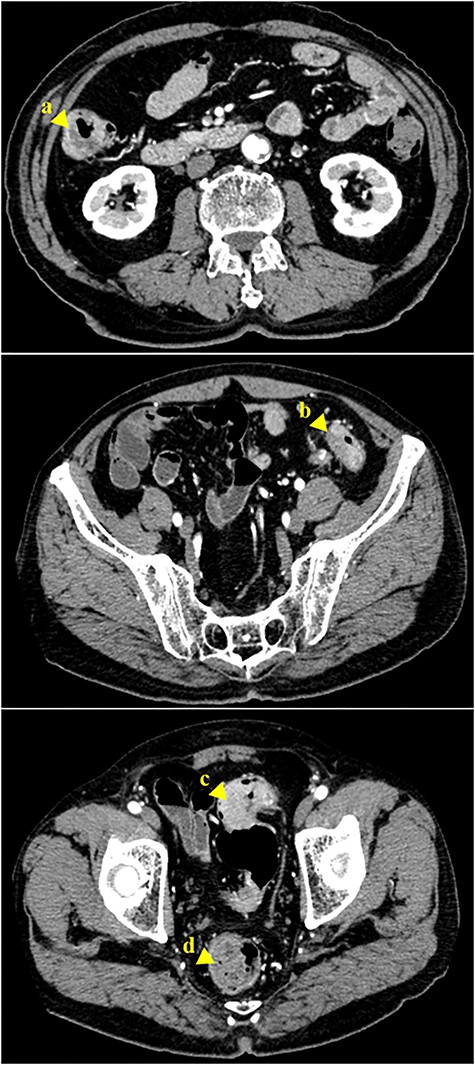

Histopathological examination of the tissue specimens revealed four tumors showing cancerous cells arranged in a tubular pattern.

According to the American Joint Committee on Cancer/Tumor-Node-Metastasis Staging System, the p-stage was IIIa, T3N1M0. The patient was discharged 15 days after surgery. For adjuvant chemotherapy, the patient chose to take an oral fluoropyrimidine agent for 6 months. Fortunately, there have been no signs of metastasis or recurrence after the operation at 64 months of follow-up.